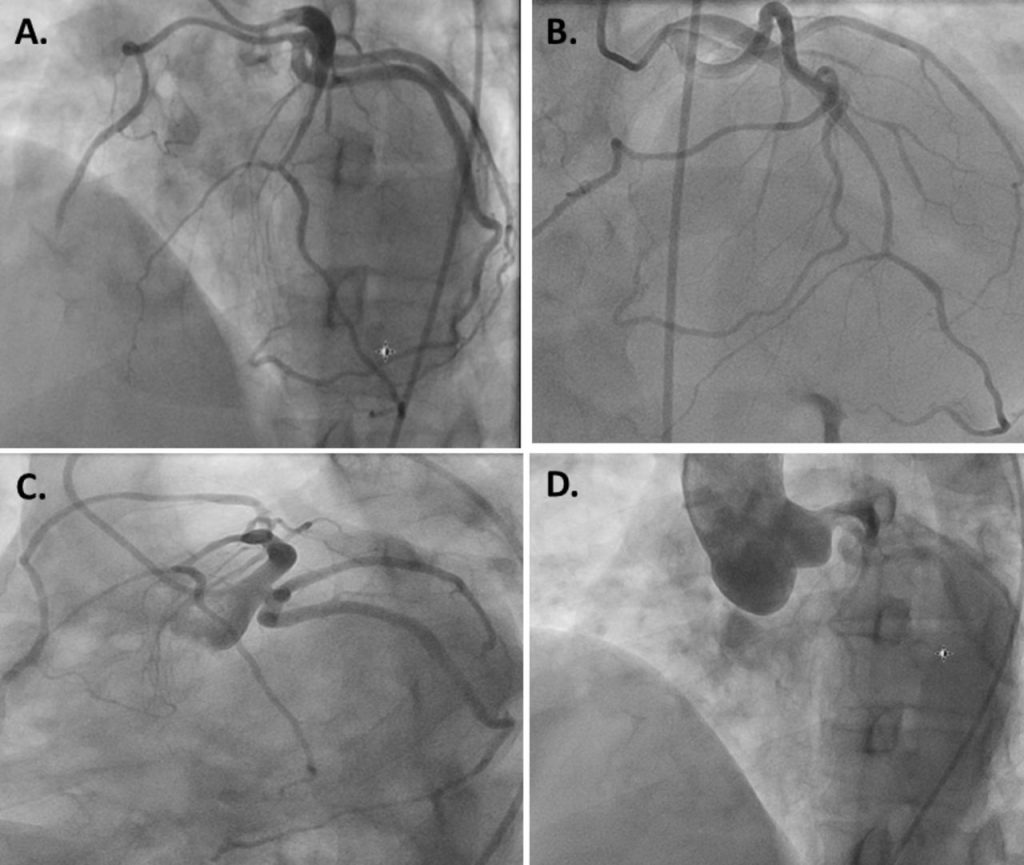

Angio-koronarografia qe eshte nje ekzaminim, qe jep informacion te detajuar dhe te sakte te eneve qe furnizojne me gjak zemren (arteriet koronare) nepermjet perdorimit te rrezeve X, duke percaktuar keshtu numrin dhe shkallen e ngushtimeve brenda arterieve koronare, si dhe menyren me te pershtatshme te trajtimit te ketyre ngushtimeve.

Koronarografia eshte nje procedure qe nepermjet kontrastit te injektuar dhe rrezeve X shikohet si rrjedh gjaku ne arteriet koronare. Ky ekzaminim realizohet duke futur brenda trupit te pacientit permes nje porte hyrese, zakonisht nje ene gjaku qe kalon ne pjesen e siperme te kofshes apo ne krah, nje tub plastik te gjate, te holle dhe fleksibel te quajtur kateter, nepermjet te cilit injektohet ne arteriet koronare lenda e kontrastit. Lenda e kontrastit ka vetinë te behet e dukshme nen veprimin e rrezeve X. Aparati i rrezeve X mundeson realizimin e nje numri imazhesh, të cilat japin informacion të detajuar mbi pamjen e brendshme te arterieve koronare.

Koronarografia realizohet ne menyre urgjente kur pacienti paraqitet ne kushtet e nje infarkti, arresti apo ataku kardiak. Koronarografia i rekomandohet atyre personave, të cilet kane simptomat e IMA si pershembull dhembje gjoksi, e cila perhapet ne nofull, qafe dhe krahun e majte gjate aktivitetit fizik, që nuk shpjegohet nga ekzaminimet e tjera, dhembje gjoksi e shfaqur për herë te pare apo dhembje gjoksi, e cila vjen duke u renduar. Gjithashtu, koronarografia realizohet kur pacienti paraqet veshtiresi ne frymemarrje, lodhje te theksuar, çrregullime te ritmit te zemres apo ulje të funksionit te zemres te cilat nuk shpjegohen nga shkaqe te tjera. Rekomandohet dhe tek pacientet e nje moshe te caktuar, te cilet do te realizojne nje nderhyrje kirurgjikale per shkak te semundjeve te valvulave te zemres apo defekteve te lindura ne zemer. Pas realizimit te koronarografise, pacienti merr nje tablo te qarte te gjendjes se arterieve koronare. Arteria korornare mund te jete pa stenoza, me stenoza jo sinjifikative, me stenoza kritike apo edhe te mbyllura plotesisht. Në varesi te gjendjes se arterieve koronare, behet dhe trajtimi i tyre.

a- Angiografia e arterieve koronare, mundeson lokalilizimin e ngushtimit te tyre, zgjerimin e menjehersheper te arteries pergjegjese per infarktin, pas vendosjese se stentes.